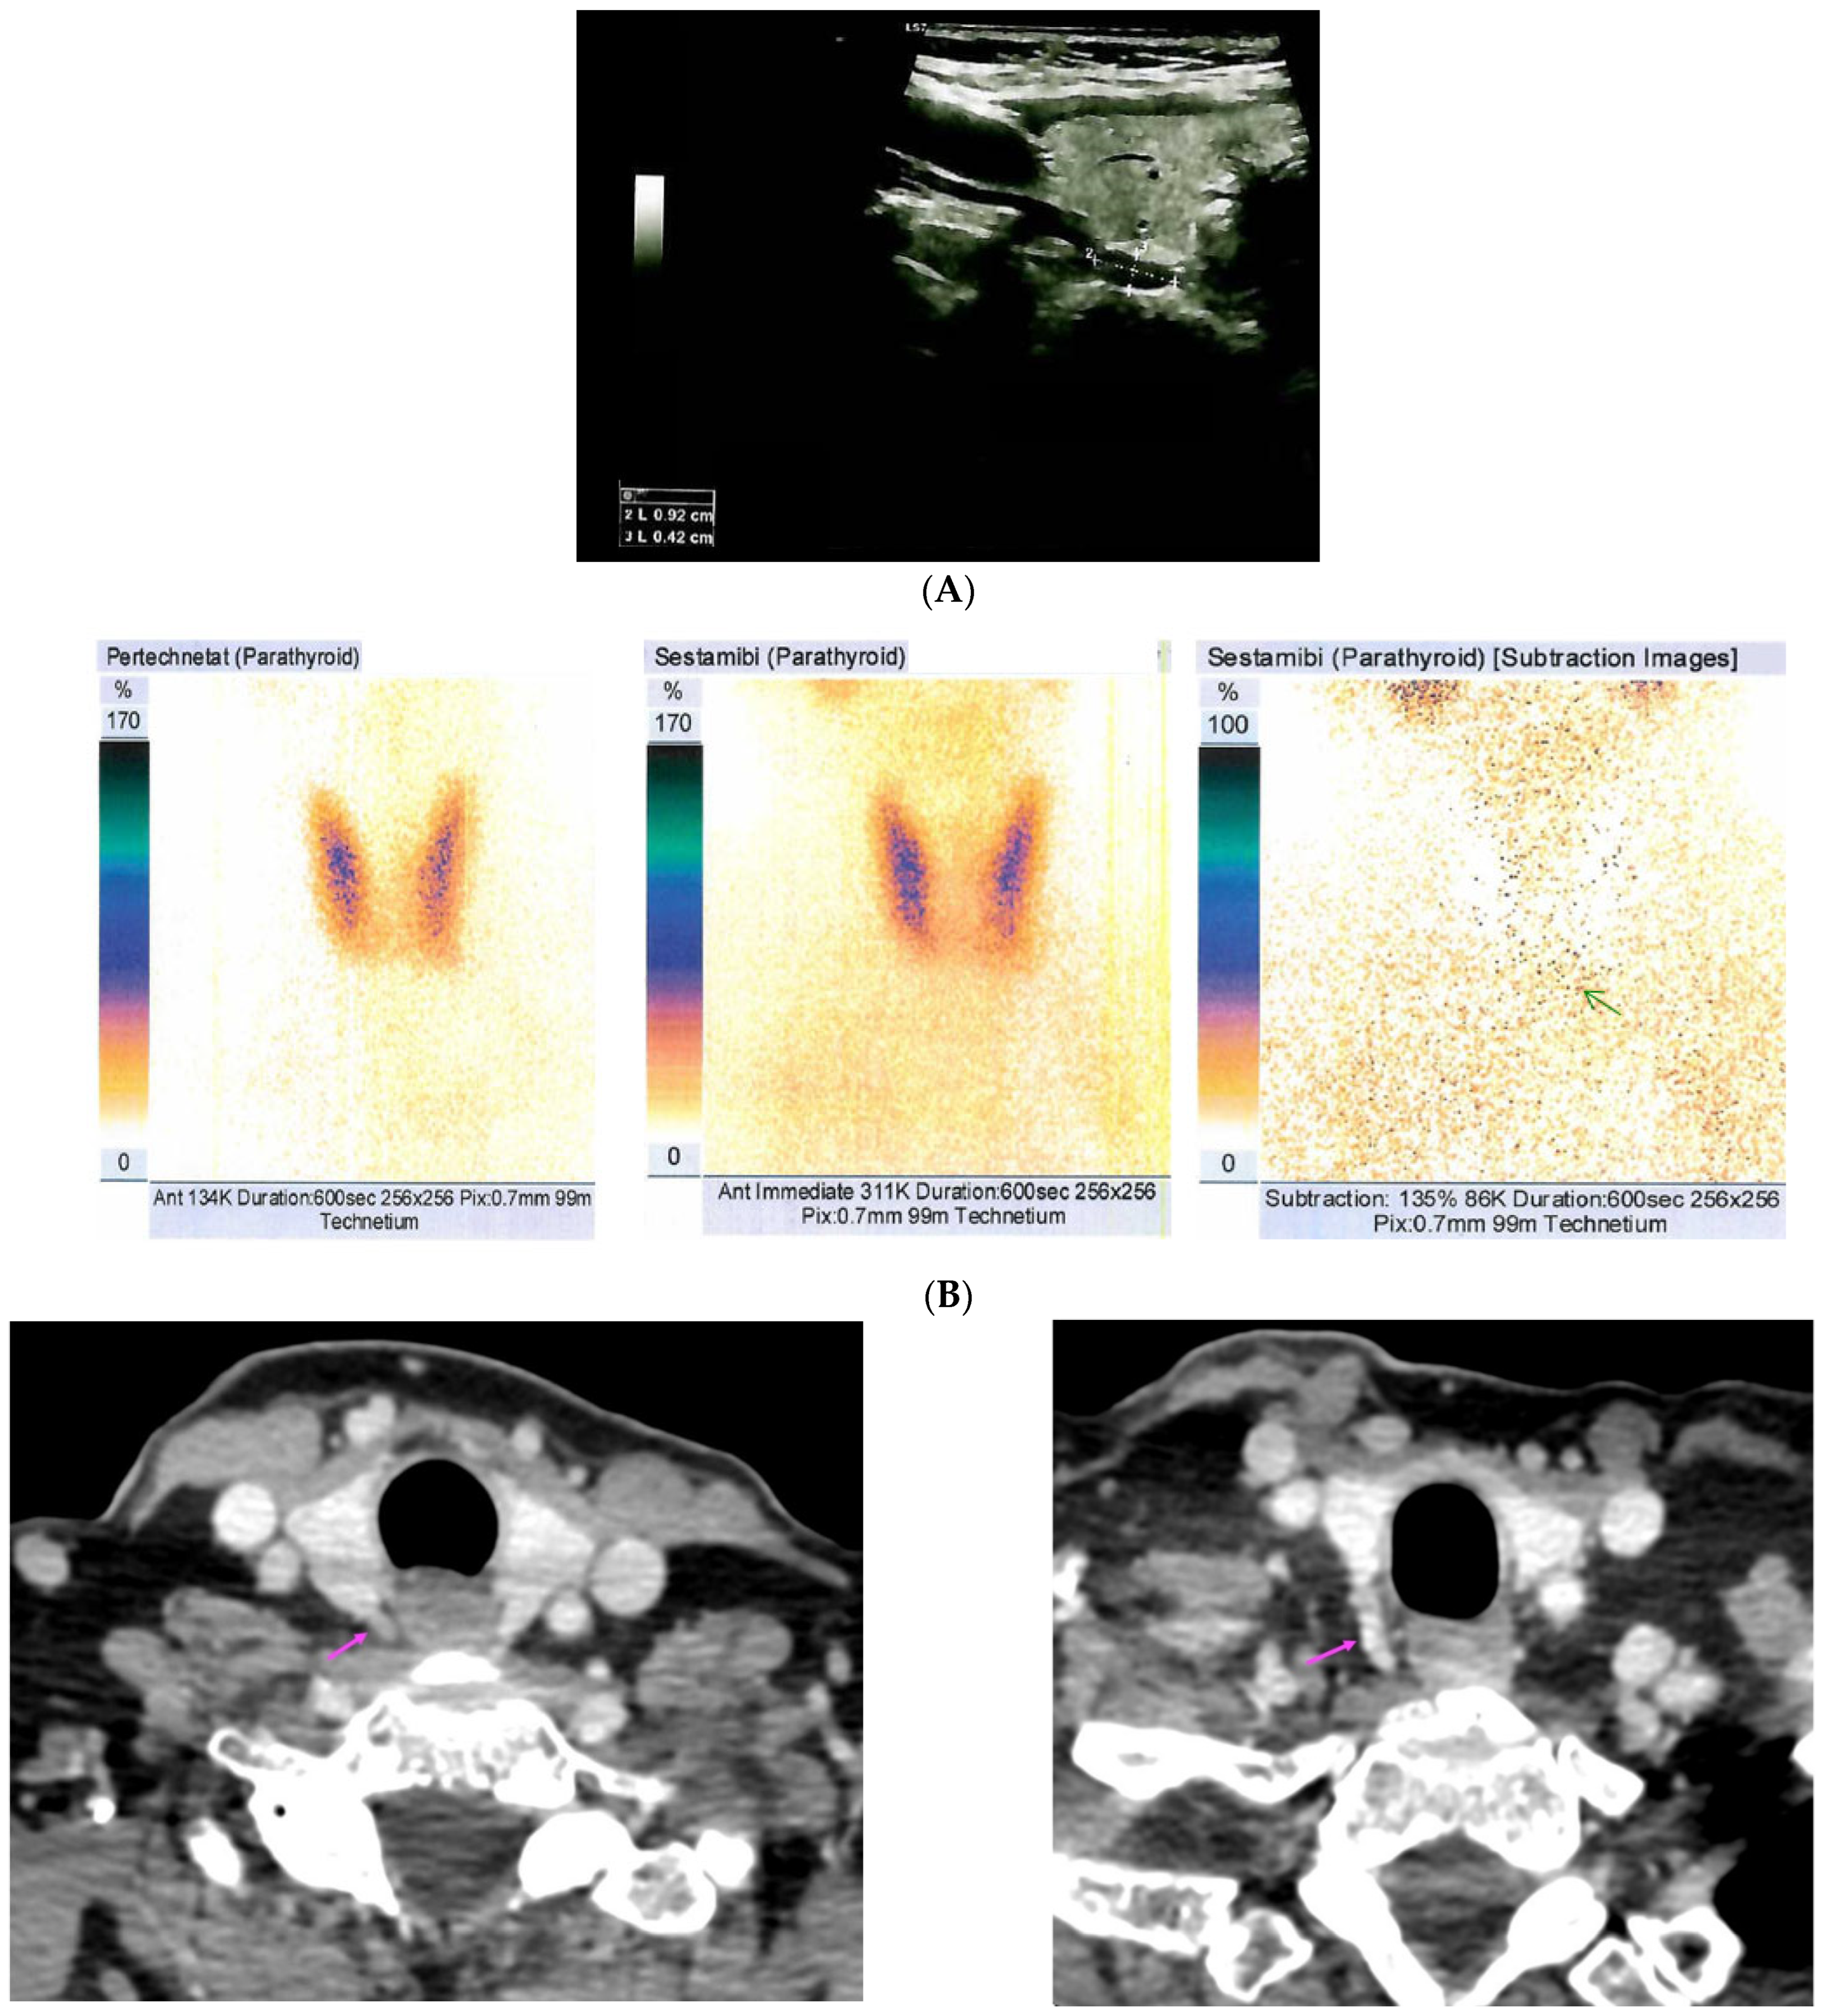

| [37] | US: six nodules of 5 mm to 16 mm located subcutaneously anterior of right sternocleidomastoid muscle 99m-Tc sestamibi scintigraphy: no hyper-functional foci CT: similar to US | Parathyromatosis |